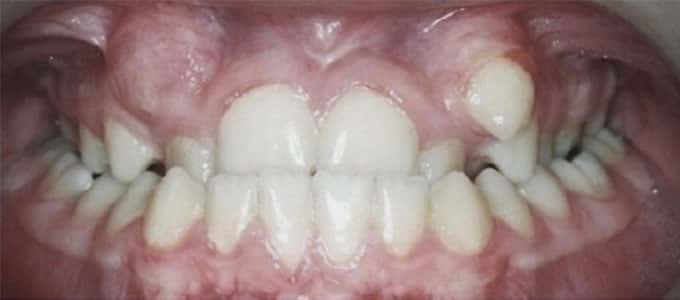

Un zâmbet frumos

Un zâmbet frumos este roada tratamentului ortodontic de succes dar pentru a se ajunge la acest rezultat sunt necesare mai multe etape care trebuie parcurse pas cu pas.

Tratamentul ortodontic este un proces biologic complex care include modificări ale oaselor maxilare, faciale și ale țesuturilor moi pe măsură ce dinții sunt mișcați în noile poziții.

Tratamentul ortodontic nu este o soluție rapidă. Acesta începe întotdeauna cu o examinare minuțioasă a dinților, a buzelor și a întregului aspect facial, sunt necesare radiografii si fotografii de diagnostic. Din aceste informații detaliate medicul ortodont dezvoltă un plan de tratament personalizat.